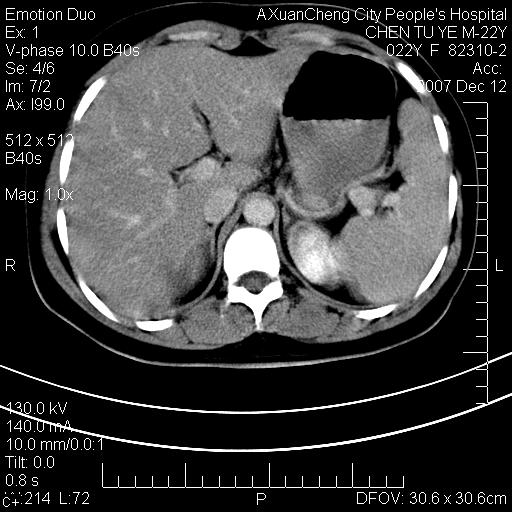

超声提示肝右前叶占位,约2.5cm.

各位战友看看病灶在什么地方,可是右前叶进肝裂部低密度影,平扫ct值约10以下,增强后增高明显

1 脾大,慢性肝损伤. 2 肝脏脂肪侵润.  3 你所指的部位疑点,我没看出有问题.

脂肪肝.楼主所指部位不考虑异常,为肝圆韧带影.

1 脾大,慢性肝损伤. 2 肝脏脂肪侵润.

不均匀脂肪浸润,版主所说的病灶为肝园韧带服着点。

考虑肝圆韧带。